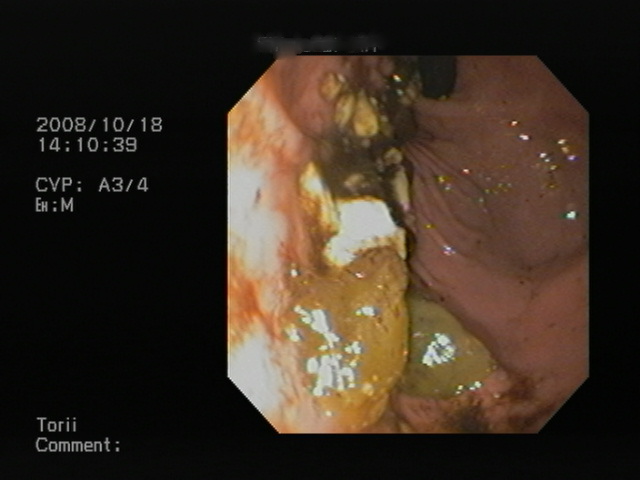

では内視鏡検査所見です。

食道の心基部の写真です。黄色い物体が引っかかっている異物です。

これを異物除去鉗子で、除去を試みました。

(分かりやすくいうと、内視鏡のカメラで見ながら、つかんでとってしまおうということです。)

これは失敗しました。

食べ物が水分をすってずいぶん柔らかくなってしまっていました。

よって、鉗子で細かく砕いて、胃の中に移動させる作戦に切り替えました。

少し移動させた写真です。

食道粘膜面の炎症が分かりますよね。

赤く充血しています。(異物が引っかかっていた場所です。)

これを、内視鏡を用いて、ゆっくりと移動させました。

胃の中の写真です。

バラバラになった、食べ物が認められます。

これで、ワンちゃんも(夢叶い)おやつを無事食すことができました。(笑)

実は胃の中から再度摘出を検討したのですが、やはりバラバラになった食べ物を取り出すことができず断念です。もともとおやつでしたので、これで一件落着と・・・

食道炎が見つかりました。

程度としては、中程度と思いましたが、要注意です。

今後の食欲の状態が心配されます。

また最悪の場合は、食道狭窄を起こしかねませんので、今後の状態が大変心配されます。